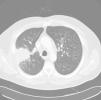

Varón de 52 años, fumador activo, que consultó por fiebre, malestar general y expectoración hemoptoica de 15 días de evolución. En la auscultación pulmonar llamaba la atención la presencia de estertores crepitantes aislados. En la radiografía de tórax se visualizaba una condensación en lóbulo superior derecho y aumento de tamaño hiliar homolateral. Se pautó tratamiento con levofloxacino con escasa mejoría, por lo que se solicitó una TC torácica que mostraba una condensación con broncograma aéreo en segmento posterior de lóbulo superior derecho (fig. 1), adenopatías hiliares derechas y en espacios pretraqueal retrocavo y prevascular. Se realizó una broncoscopia, macroscópicamente normal, con muestras citológicas y baciloscopia de aspirado bronquial sin anomalías. Por ello se programó una biopsia pulmonar con aguja gruesa guiada por TC, cuyo estudio histológico reveló la presencia de granulomas con células gigantes multinucleadas e histiocitos transformados tipo célula epitelioide, alguno de ellos con necrosis central. Se comenzó tratamiento con isoniacida, rifampicina, piracinamida y etambutol. Posteriormente se aisló en el cultivo de micobacterias del aspirado bronquial, M. interjectum, utilizando tecnología de ADN basado en la hibridación inversa de los productos de PCR dirigidos a la región del gen 23S rRNA (GenoType®Mycobacterium CM). La evolución fue satisfactoria y al segundo mes el cultivo de micobacterias fue negativo. Se mantuvo el régimen terapéutico, retirando pirazinamida y etambutol, continuando con isoniacida y rifampicina hasta completar un año, momento en el que el paciente se encontraba asintomático, mostrando la radiografía de tórax un infiltrado fibrocicatricial en lóbulo superior derecho. En la actualidad, 20 meses después, permanece estable sin evidenciarse reactivación de la enfermedad.